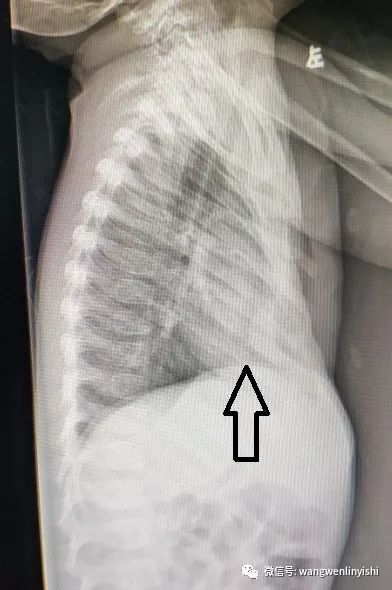

前来公布答案:poland综合征 这个患者的胸壁,肩胛肌群缺失的如果能

典型病例poland综合症